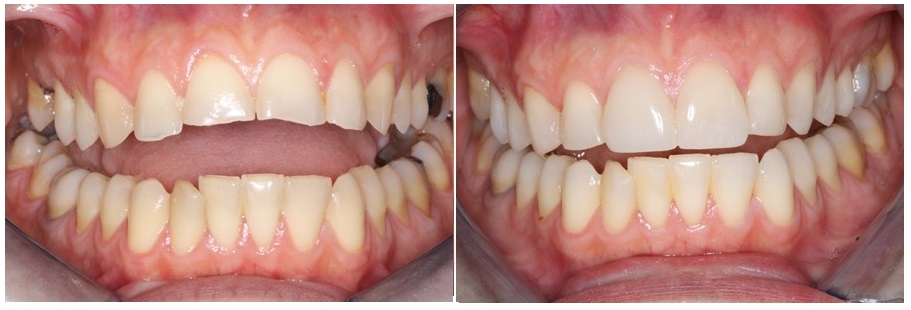

Σήμερα θα δούμε μαζί πως αντιμετωπίσαμε ένα περιστατικό διάβρωσης των δοντιών από εμετούς, σε ασθενή που υπέφερε από υπερέμεση σε όλη την διάρκεια δύο κυήσεων.

Τα δόντια της ασθενούς είχαν διαβρωθεί σημαντικά, ειδικά στις πίσω πλευρές των μπροστινών δοντιών και στις μασητικές επιφάνειες των άνω δοντιών, όπως φαίνεται στην φωτογραφία που ακολουθεί.

Σιγά σιγά όμως, η απώλεια οδοντικής ουσίας επεκτείνεται και στο κοπτικό χείλος των πρόσθιων δοντιών τα οποία μειώνονται σε πάχος, φθείρονται από την χρήση, αποδίδοντας στο χαμόγελο της ασθενούς μας μη ελκυστική εμφάνιση.

Στα προχωρημένα στάδια της νόσου εμφανίζονται συνήθως αλλαγές και στα πίσω δόντια τα οποία καθώς διαβρώνονται μικραίνουν σε μέγεθος, οδηγώντας μερικές φορές και σε απώλεια της κάθετης διάστασης του προσώπου.

Στο περιστατικό μας οι βλάβες ήταν λιγότερο έντονες στα κάτω δόντια, τα οποία σε σύγκριση με τα δόντια της άνω γνάθου διατηρούσαν την μορφολογία τους.

Η ασθενής αποφάσισε να αντιμετωπίσει το πρόβλημα, όταν τα κοπτικά άκρα των πρόσθιων δοντιών έσπασαν και έχασαν προοδευτικά το σχήμα τους οπότε και το αισθητικό πρόβλημα έγινε πιο έντονο.

H τελική εικόνα του περιστατικού είναι πολύ ικανοποιητική.

Οι όψεις πορσελάνης ολοκλήρωσαν την θεραπεία και έδωσαν στην ασθενή μας ένα νέο υγιές χαμόγελο.